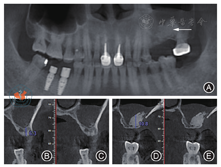

术前抽血25 ml制备富血小板纤维蛋白(platelet-rich fibrin,PRF)膜以备用。常规消毒后,局麻下沿25、26牙槽嵴顶偏颊侧做"梯形"切口,翻瓣,开窗后剥离上颌窦膜,推余留骨质向窦腔,放置1片PRF膜,充填骨粉(1.5 g,Bicon,美国),放置胶原膜(2.0 cm × 2.5 cm,海奥口腔修复膜,烟台)后覆盖PRF膜,严密缝合创口(图2)。术后CBCT示:25区骨质较厚,约6.3 mm,骨粉较少;26骨粉高度约10 mm。植骨区与窦腔内炎症区分界明显,窦膜完整(图3)。

注:图3A为植入骨粉后的全颌曲面断层影像,白色箭头处为植入骨粉;图3B~ 3C为25植入骨粉后唇颊侧切面;图3D~ 3E为26植入骨粉后唇颊侧切面